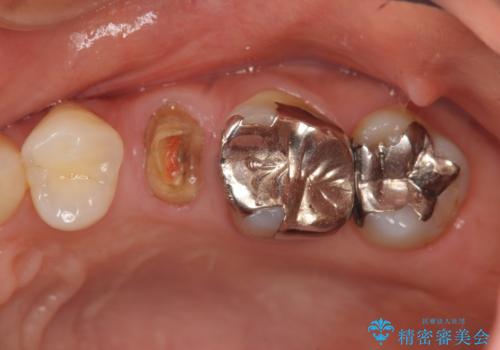

[銀歯の下の虫歯 ] 根管治療を伴う虫歯治療

![[銀歯の下の虫歯 ] 根管治療を伴う虫歯治療の症例 治療前](https://seimitsushinbi.jp/wp/wp-content/uploads/2020/05/89abd4c7a23874a1d4cee7f019e38bac-500x350.jpg?v=1590579075)